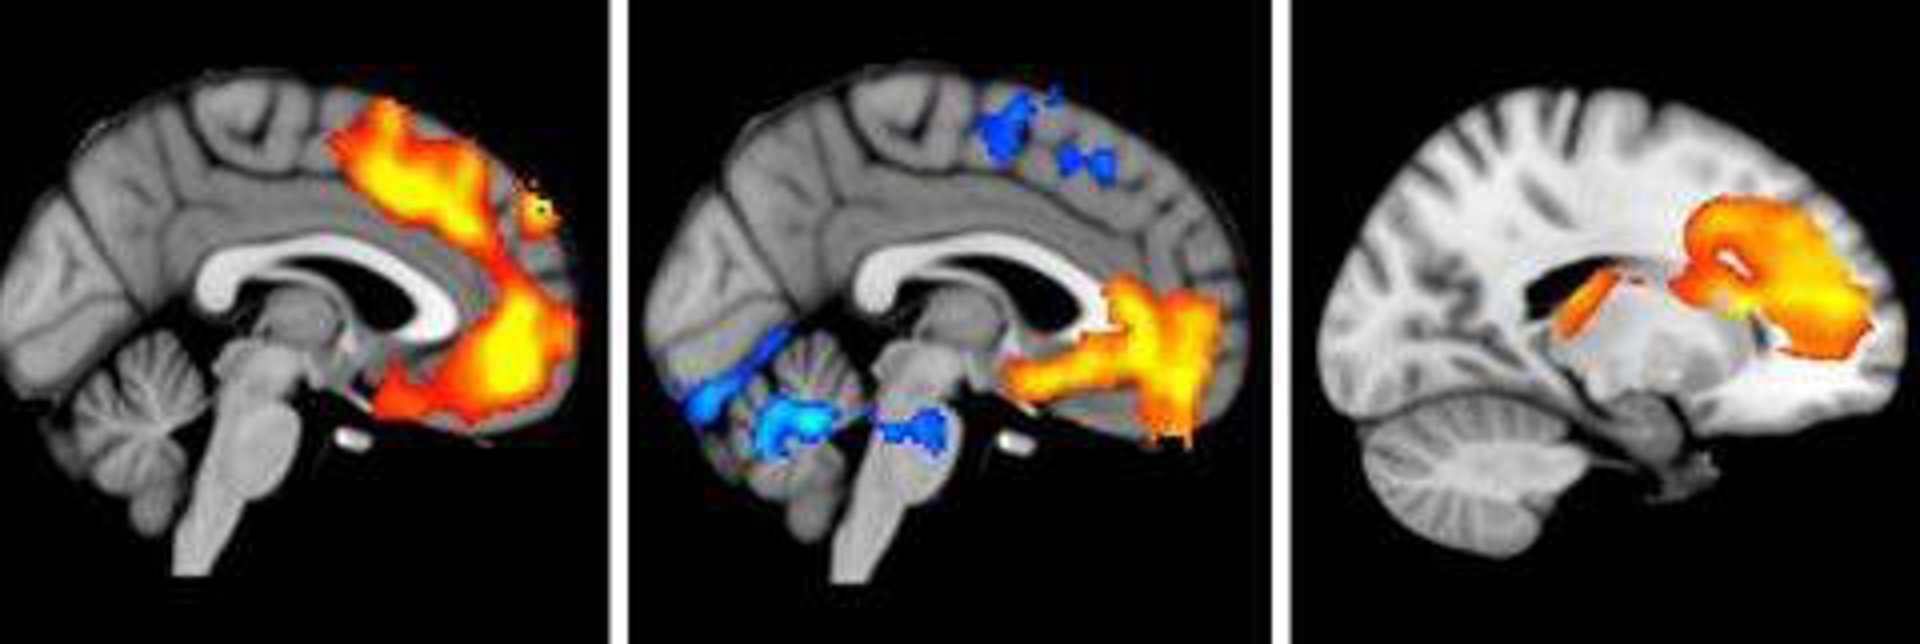

Desvelan el vínculo biológico entre estrés, ansiedad y depresión

Científicos de la Universidad de Western Ontario en Canadá han descubierto el vínculo biológico entre estrés, ansiedad y depresión. Al identificar el mecanismo de conexión en el cerebro, la investigación muestra cómo el estrés y la ansiedad podrían conducir a la depresión.

El mecanismo de vinculación supone la interacción entre el receptor 1 del factor de liberación de la corticotropina (CRFR1) y tipos específicos de receptores de serotonina (5-HTRs). Nadie antes había conectado estos dos receptores en un nivel molecular y el estudio revela que CRFR1 aumenta el número de 5-HTRs en la superficie de las células del cerebro, lo que puede causar una señalización cerebral anormal.

Dado que la activación de CFR1 conduce a la ansiedad en respuesta al estrés y que 5-HTR conduce a la depresión, la investigación muestra cómo los mecanismos de estrés, ansiedad y depresión se conectan a través de procesos distintos en el cerebro. Además, el inhibidor desarrollado por el laboratorio de Ferguson bloquea en los ratones a 5-HTR en el mecanismo para combatir la conducta de ansiedad y la potencial depresión.